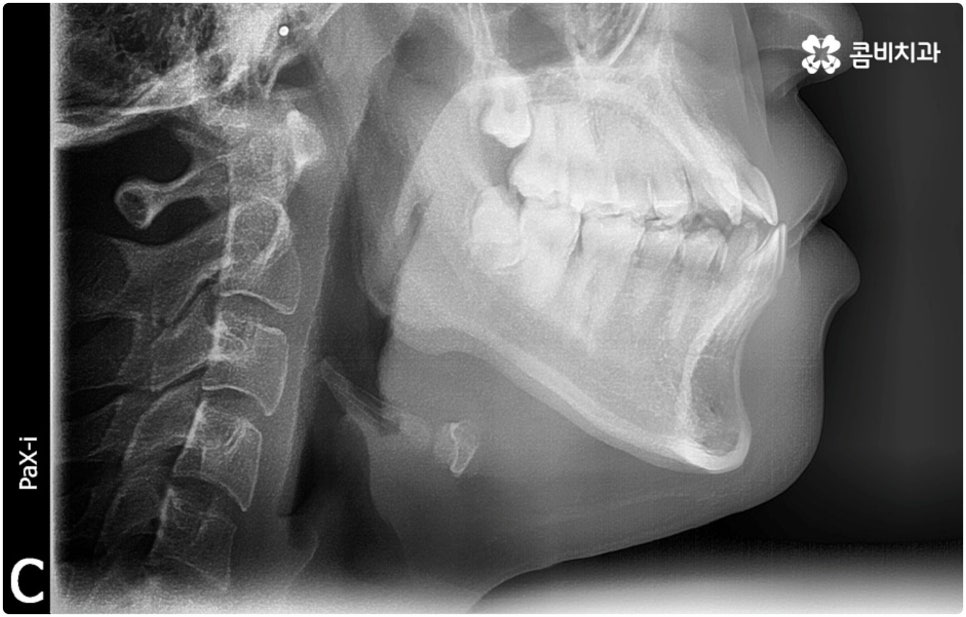

환자분들마다 상황은 모두 다르기 때문에 부정교합 교정 치료를 할 때는 정밀 검진 후 맞춤 치료 계획에 따라 무리하지 않게 진행하는 것이 중요한 포인트라고 할 수 있어요. 이때 구강내 상태 (치아, 잇몸, 치열, 교합 등) 뿐 아니라 구강 외 상태 (뼈의 위치 및 구조 발달, 얼굴 정면과 측면 등 안모 비율) 와 같은 모든 부분을 꼼꼼하게 촬영하고 환자의 연령 및 생활 습관 등을 종합적으로 고려하여 원인을 분석한 다음 치아를 어떻게 얼마나 움직여야할지 면밀하게 교정 플랜을 세우는 것이 필요하므로 3D CT, 모르페우스 같은 정밀 진단 기계를 갖추고 있는 치과에서 다양한 임상 경험을 통해 뛰어난 기술력을 가지고 있는 담당의 선생님께 치료 받으시길 권유드리고 있습니다.